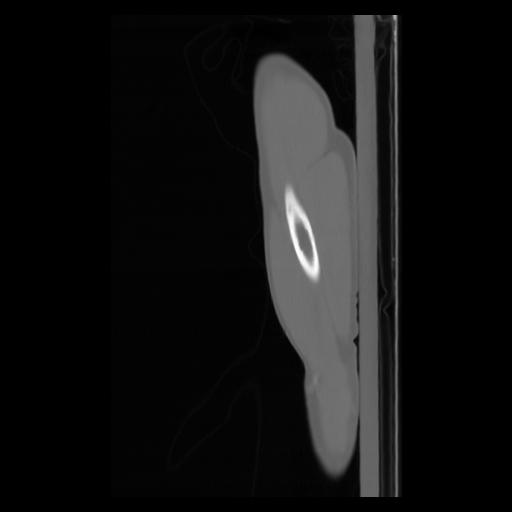

30 CUERPO,CE,Sagittal,3.000,CUERPO,Sagittal,